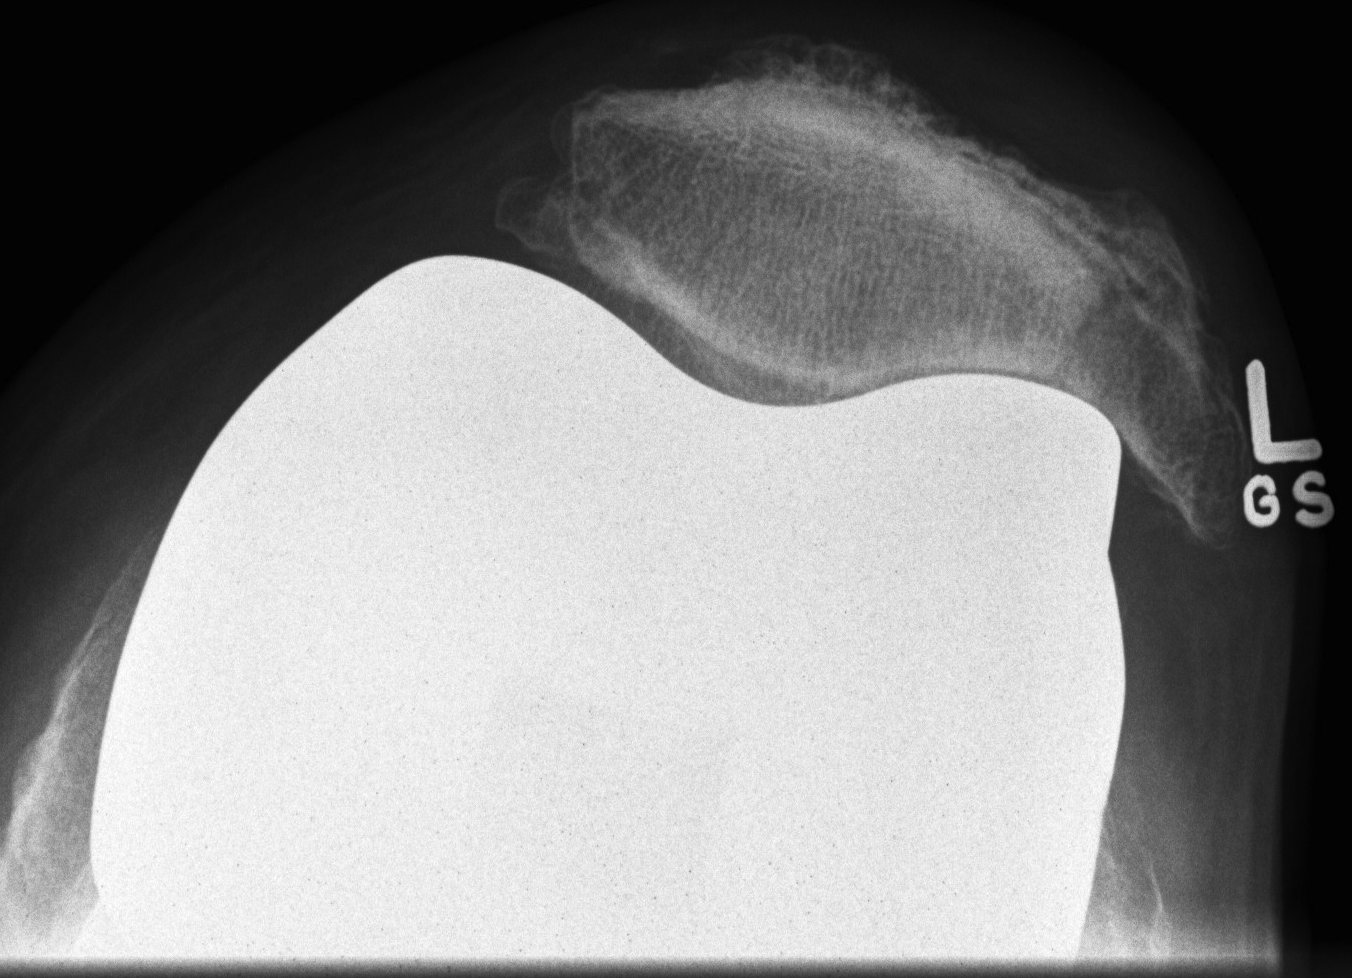

Xray

- skyline views

- lateral tilt / subluxation